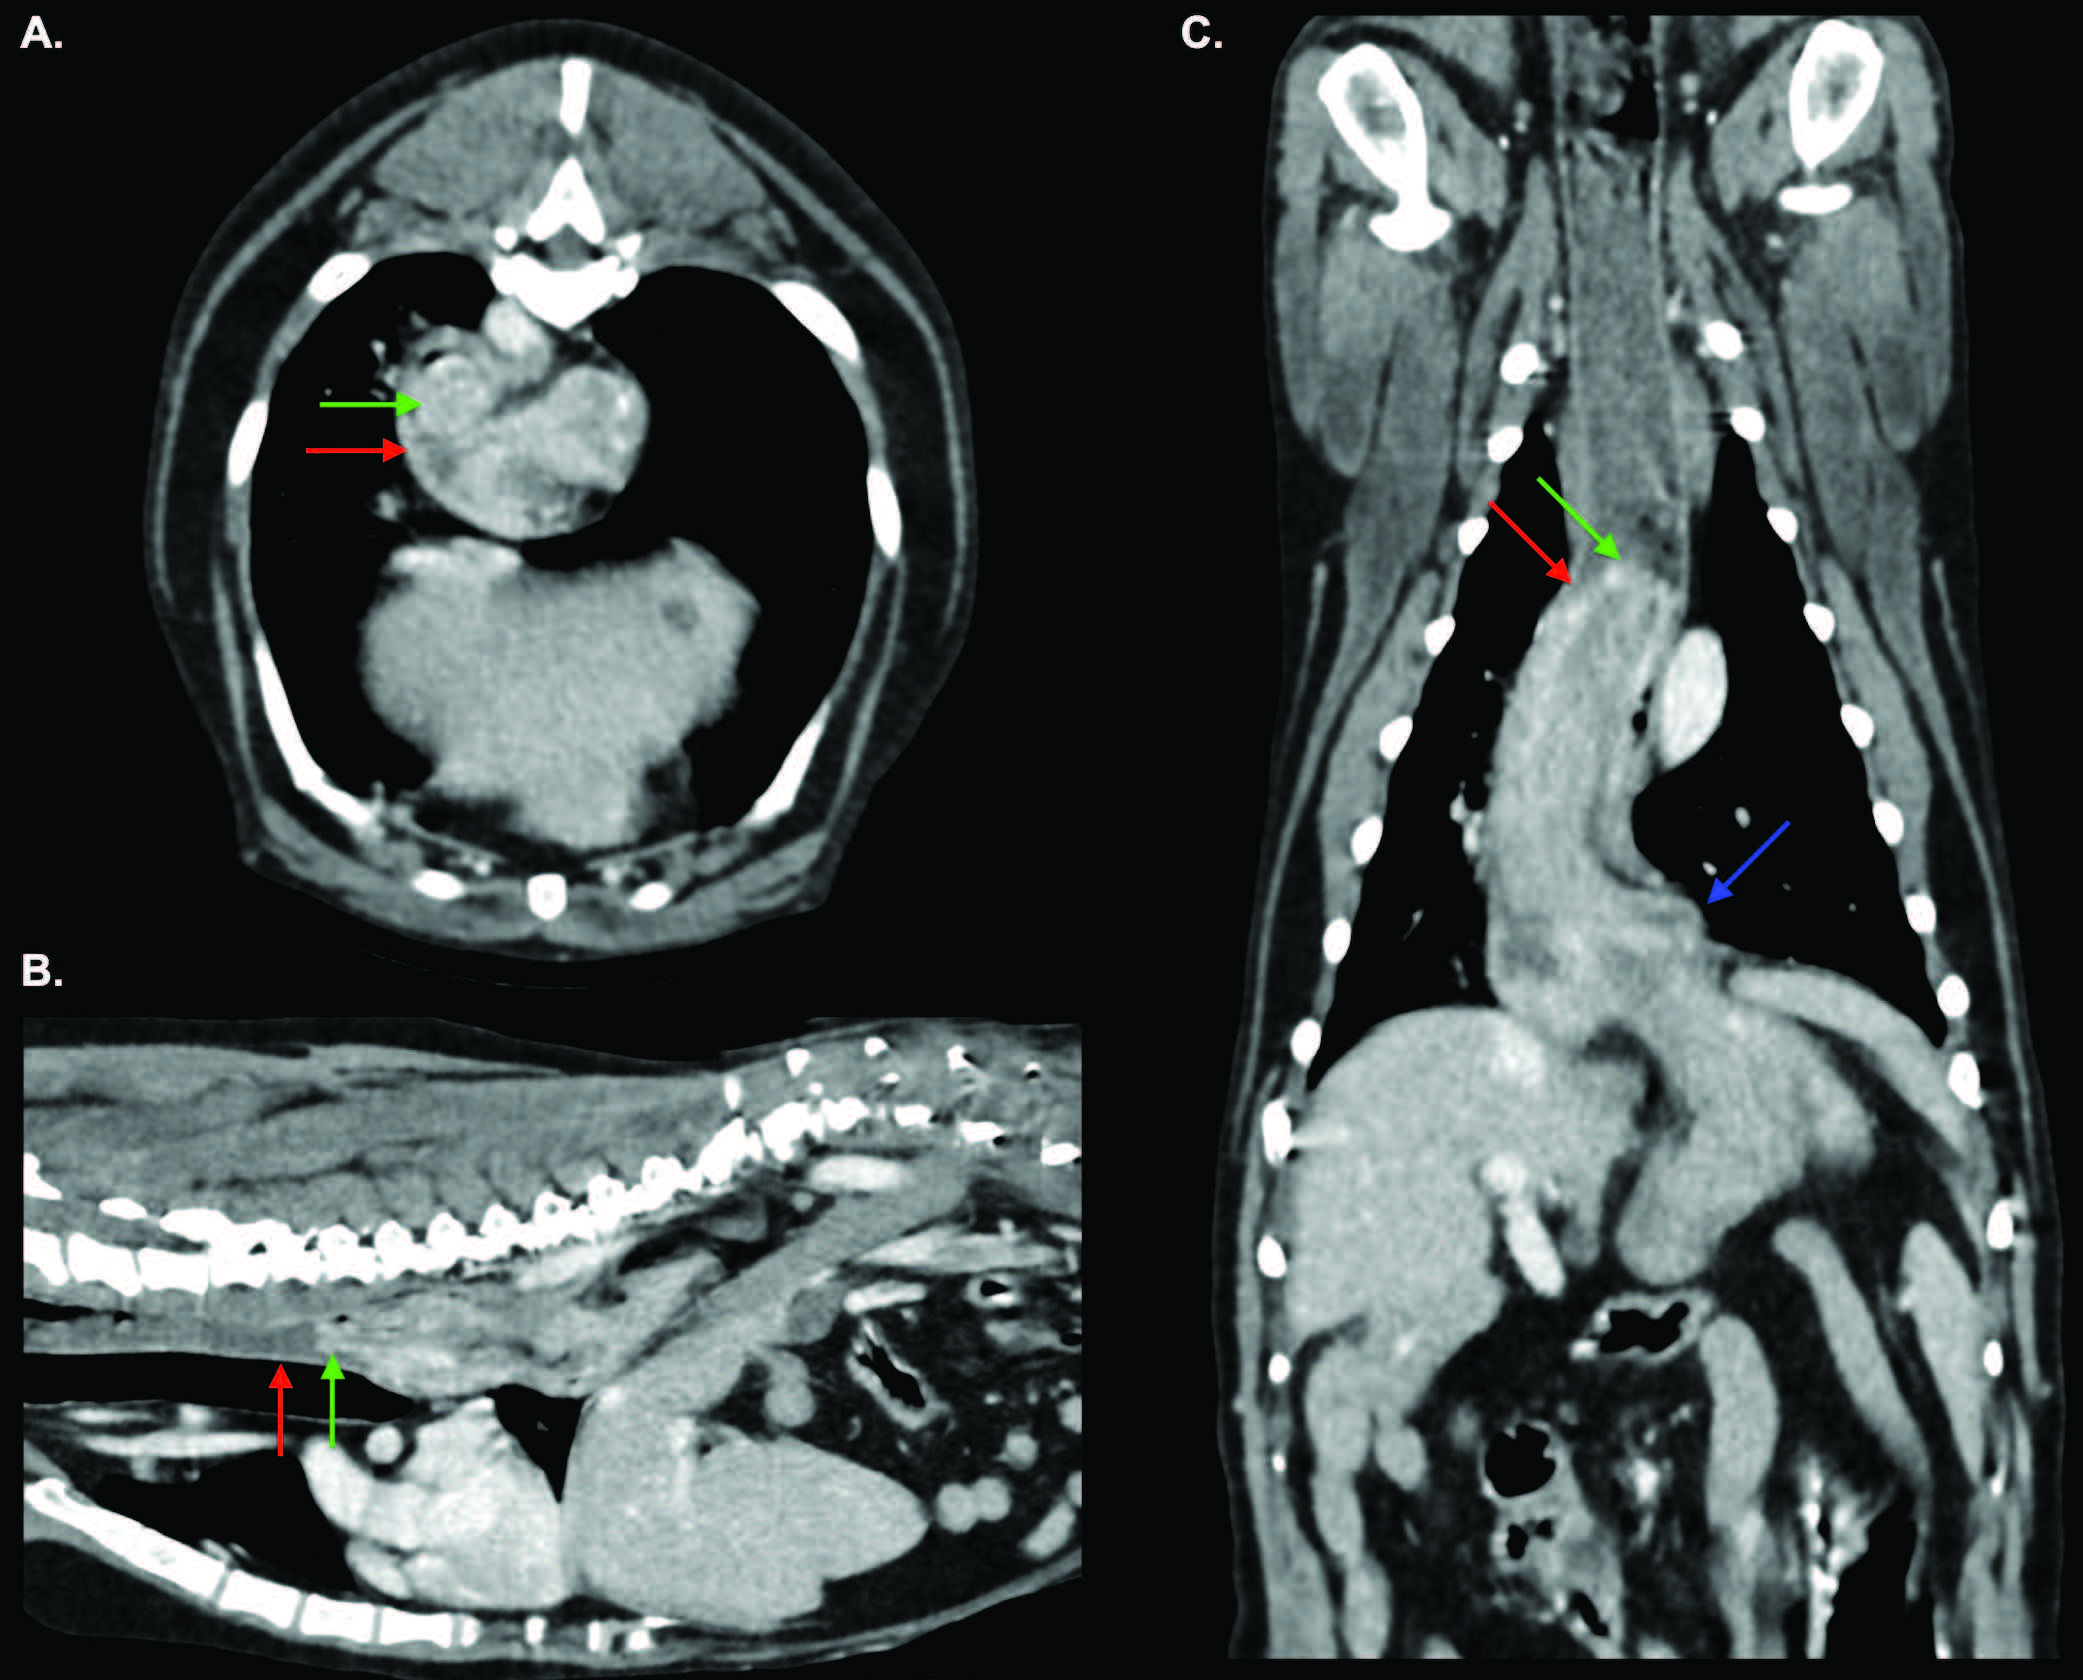

为进一步明确超声所见病变并寻找潜在转移灶,行头、胸、腹部增强CT检查。平扫示胃位置正常;静脉期增强扫描见胃底经食管裂孔向前疝入远段食管腔(图1-2)。远段食管壁部分包绕胃底,横断面呈“靶征”(图3)。食管前段含少量至中等量混杂密度液-软组织物质。延迟期图像显示胃已回纳至正常解剖位置。

图1. 静脉期横断(A)、矢状(B)与背侧(C)图像。部分胃底(绿箭头)经食管裂孔向前疝入胸段远侧食管(红箭头)。胃食管连接部(蓝箭头)位置正常。更近端胸食管被少量混杂密度、液-软组织性腔内物质轻度撑开。所见符合胃食管套叠。

胃部改变符合一过性、可自行复位的胃-食管套叠(GEI)。可能为单次、自发性GEI,或由碘海醇诱发恶心、麻醉致下食管括约肌松弛或两者共同触发;亦可能为偶然捕捉到的慢性、间歇性GEI,与静脉对比剂或麻醉无关。若属后者,该套叠可为既往滑动型食管裂孔疝的进展/加重,或为一独立、并发、间歇发生的疾病实体。